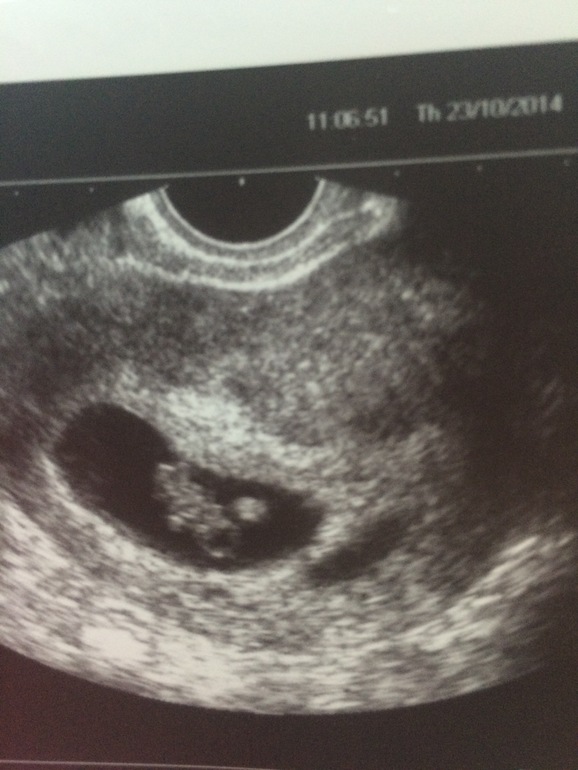

Ну вот и сходили мы вчера на УЗИ - это был 40 дпп - и акушерский срок 8 нед. и 2 дня

И вот она моя долгожданная радость! 1 Малыш ,по размерам соответствует 8 нед 2 дням,сердечко колотится 130-132 уд., сильный,крепкий малыш, уже видно все черты маленького человечка , даже уже шевелится там, правда это больше походит на спазматические движения,но это ведь еще только начало.

Я очень счастлива !!!вот мое чудо